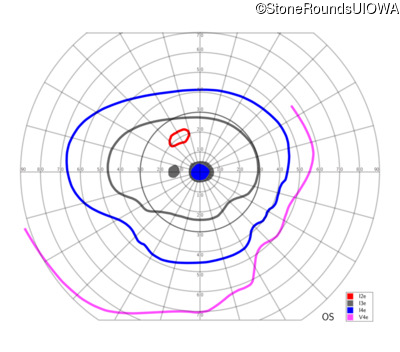

This 52 year old man had normal vision until his mid 30's when he began to have trouble distinguishing colors. the issuing 10 years he had a gradual loss of visual acuity accompanied by increasing photophobia.

| Age at visit: 55 years |

| Age at visit: 58 years |

| Age at visit: 61 years |

| Age at visit: 64 years |